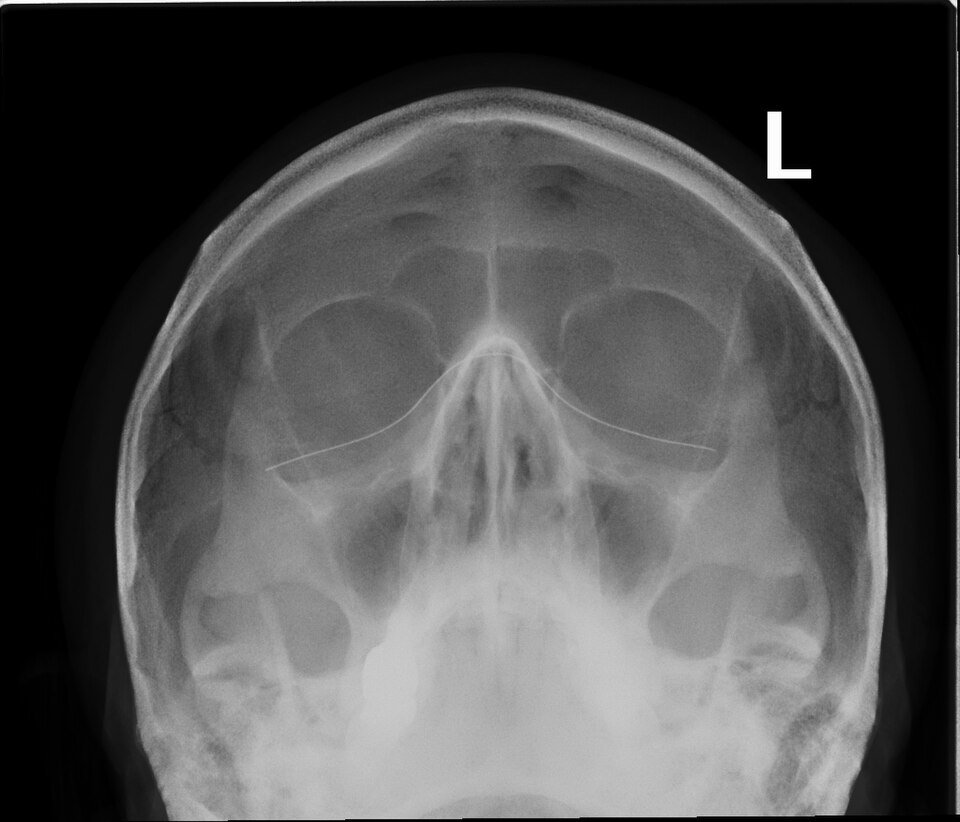

Рентген околоносовых пазух (OM‑проекция) — микророботы против насморка - nicetry.blog

Рентген околоносовых пазух (OM‑проекция). Автор: Ptrump16. Лицензия: CC BY‑SA 4.0.